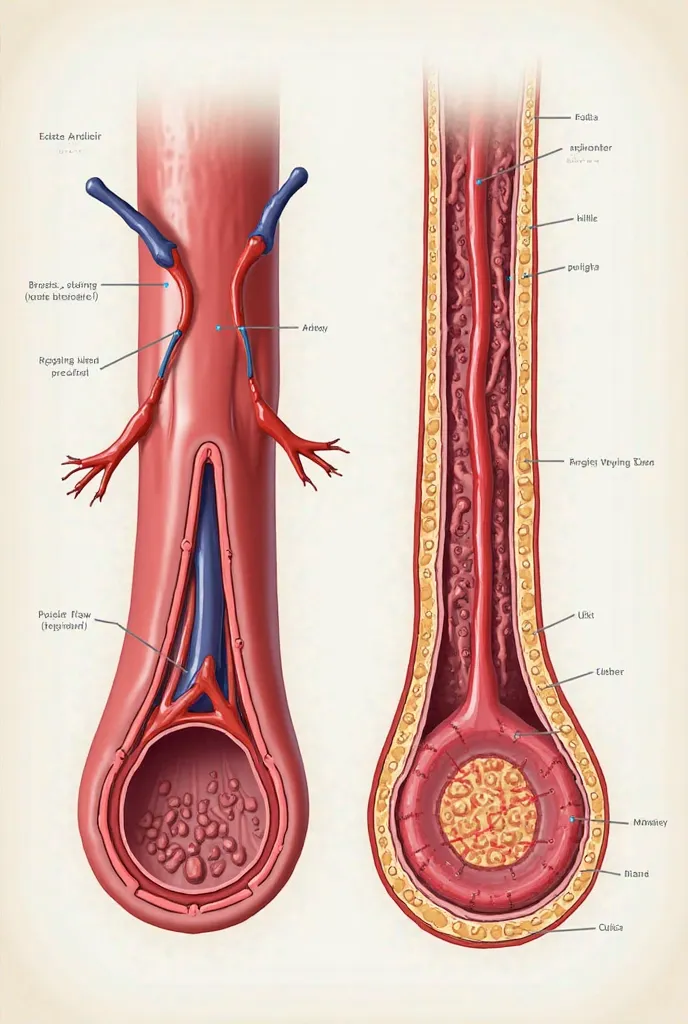

A diagram of the anatomy of the human body

Realice un dibujo de la piel. Coloque las siguientes referencias: Epidermis Fermis Hypodermis Keratinized squamous stratified epithelium Hair Sebaceous gland Sweat gland Pilo erector muscle Connective tissue Blood vessels Nerves Adipocytes

Epidermis Fermis Hypodermis Keratinized squamous stratified epithelium Hair Sebaceous gland Sweat gland Pilo erector muscle Connective tissue Blood vessels Nerves Adipocytes